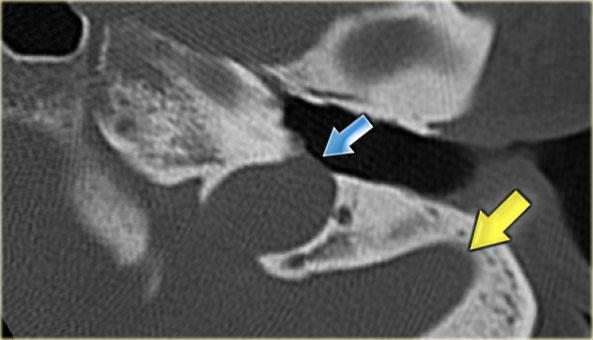

Bên trái là hình ảnh của một bé trai 16 tuổi, được khám tiền phẫu vì cholesteatoma tai phải.

Là một phát hiện tình cờ, có hình ảnh ống bán khuyên ngoài phình to (mũi tên vàng) và vắng mặt ống bán khuyên trên (mũi tên xanh dương).

Tại vị trí dự kiến của ống bán khuyên trên chỉ quan sát thấy một gờ nhỏ.

Ống bán khuyên sau bình thường.